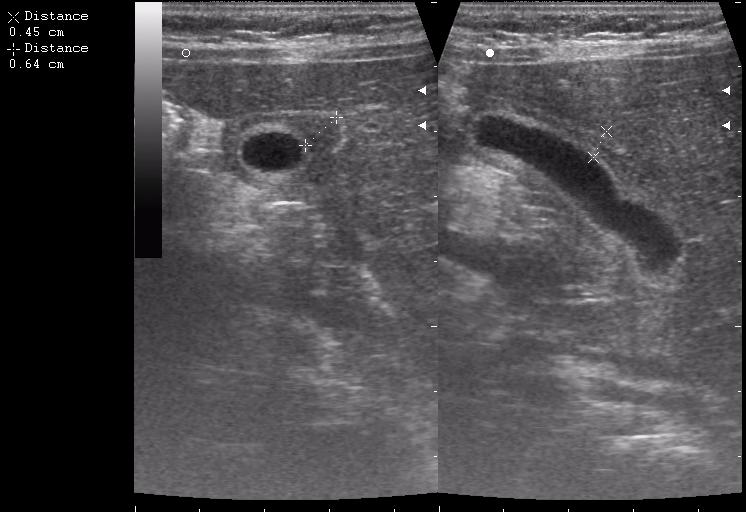

8-ми месячная девочка

По моему имеется утолщение стенки ж.пузыря по переднему контуру с частичным прерыванием наружного слоя(что-то врастает в стенку?Рядом печень имеет измененую структуру в виде некоторой неоднородности?)Надо исключить опухоль методом КТ

Имхо отек стенки. Наиболее частая причина - гепатит, также встречалось такое при психогенной анорексии (безбелковый отек).